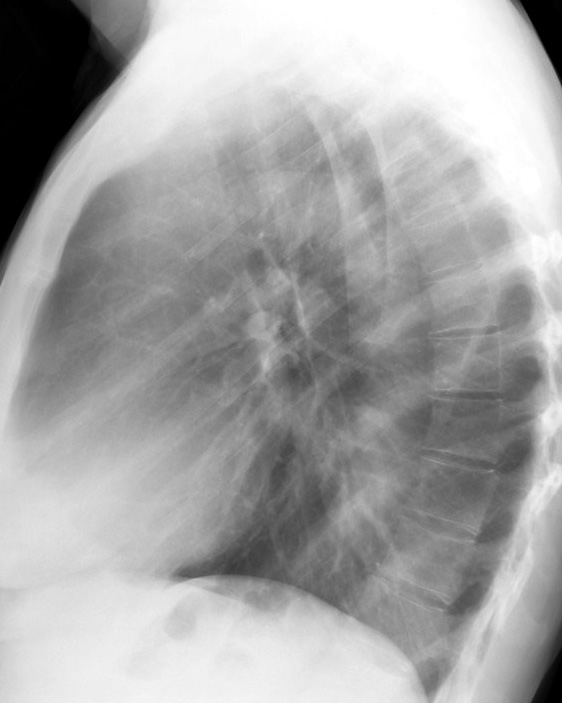

RLL Collapse  1 Lateral